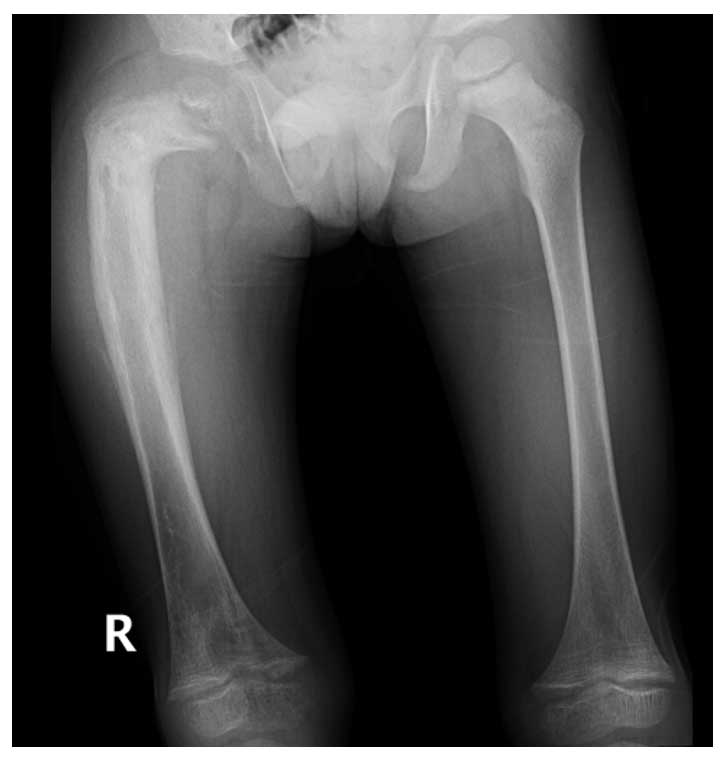

Ameliyat Öncesi: Röntgende sağ proksimal femurda deformite düzensizlik ve periost reaksiyonu görülmekte.